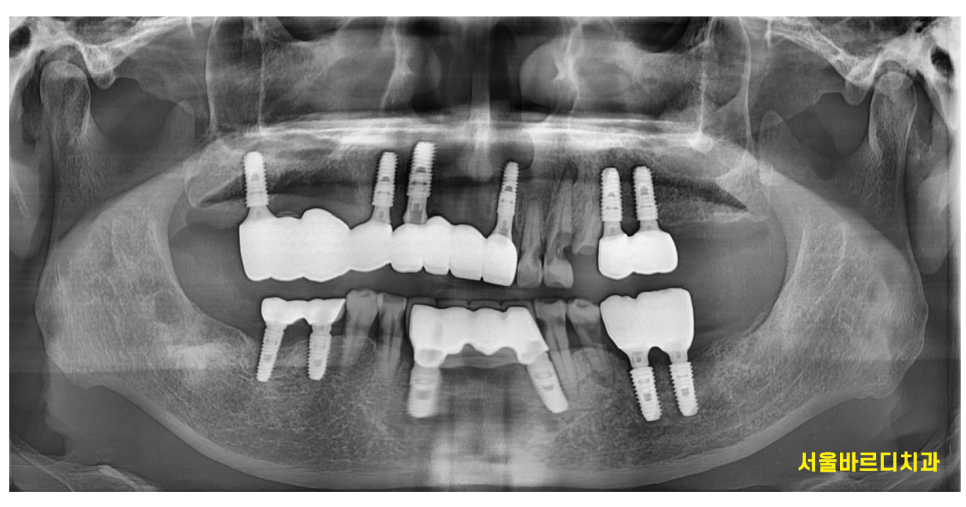

천호동 치과 치료의 끝나고 촬영한 X RAY입니다.

CT대로 분석하고 임플란트를 하다보니

처음 계획대로 치료가 완료되었습니다.

이제 위 아래 치아끼리 맞물리니

빠른 시기로 충치가 많이 먹은 치아들을 치료하는 것으로

2차 계획을 세워야겠습니다.